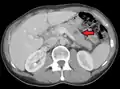

- Liver metastasis: hepatomegaly (enlarged liver), nausea[9] and jaundice[9]

Metastatic tumors are very common in the late stages of cancer. The spread of metastasis may occur via the blood or the lymphatics or through both routes. The most common sites of metastases are the lungs, liver, brain, and the bones.[10]

This is typical route of metastasis for sarcomas, but it is also the favored route for certain types of carcinoma, such as renal cell carcinoma originating in the kidney and follicular carcinomas of the thyroid. Because of their thinner walls, veins are more frequently invaded than are arteries, and metastasis tends to follow the pattern of venous flow. That is, hematogenous spread often follows distinct patterns depending on the location of the primary tumor. For example, colorectal cancer spreads primarily through the portal vein to the liver.